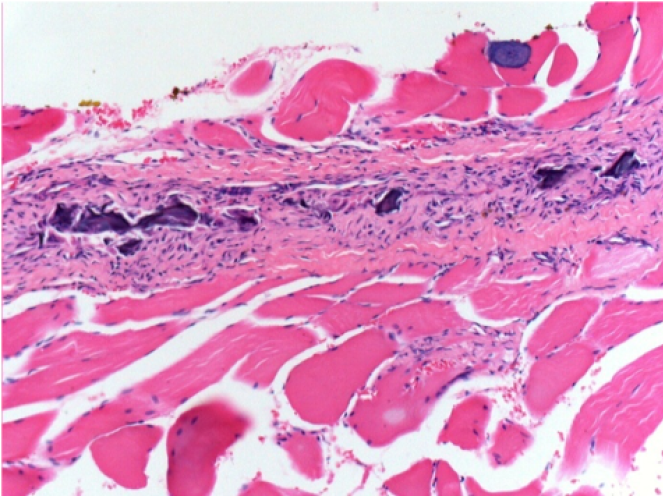

Endopeel Injection in Subcutaneous Tissue

0.5 ml ( 5x 0.1ml) Endopeel SC Injection in the right subcutaneous pretibial area.

L:200x-Control-SC

R-D10-SC-200X

R-D30-SC-200X

R-D90-SC-200X

R-D210-SC-200X

R-D210-SC-400X

- Endopeel induces a selective reversible myofibrolysis and inflammatory reaction on a period of 1 month, approximately

- Muscular changes are reversible in almost full totality

- The muscle is the better place to inject Endopeel because of more efficacity, control and duration of its action

- No necrosis nor abcess have been found all over the study.